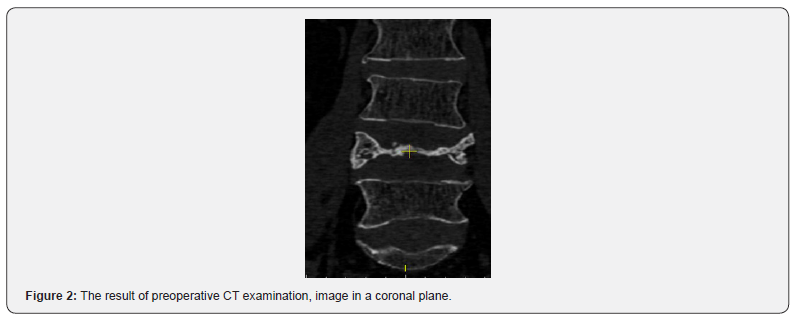

A considerable axial pain relief was evaluated in 21 case, no cases with pain intensity over 4 (VAS) and ODI over 40% were detected. No resorption of material used for screw augmentation was detected during the follow-up period, augmented parts of vertebrae remained hyperdense. Application of the suggested technique can be demonstrated by a clinical case. The patient was treated because of osteoporotic OF4 fracture of L4 vertebra. The calculated radiodensity came to 65 HU, the T criterion by DXA value accounted for -3,5. Patient underwent L3-L4-L5 pedicle screw fixation with suggested technique of augmentation. As only axial pain was present and no neurological symptoms were detected nerve root decompression was not performed. Preoperative results of CT examination are present in (Figures 1 & 2). Postoperative CT images and results of CT examination 18 months after are presented in (figures 3- 6) respectively.